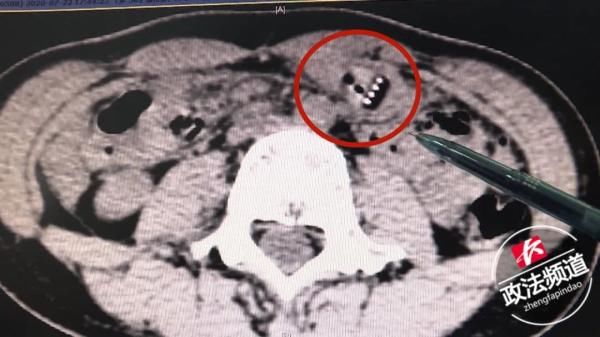

医生立即给小雨进行CT检查,在其胃下部近胃窦区看到牙刷状低密度异物影。若不及时取出,可能给胃部造成严重损伤甚至大出血。

▲CT显示牙刷位置